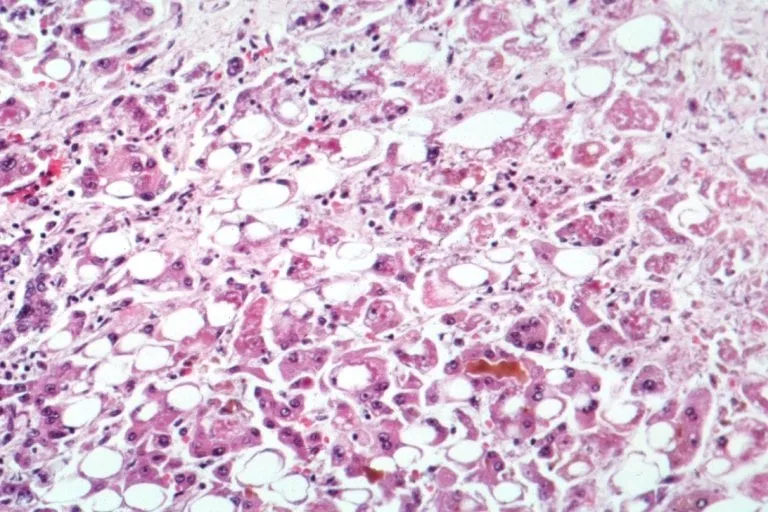

Microscopie du foie montrant des signes d'hépatite alcoolique

5/5

Creative Commons

Crédit : Author The original uploader was Countincr at English Wikipedia - Licence : https://creativecommons.org/licenses/by-sa/2.5/

L'hépatite alcoolique aiguë est une affection sévère du foie liée à la toxicité indirecte de l'alcool.